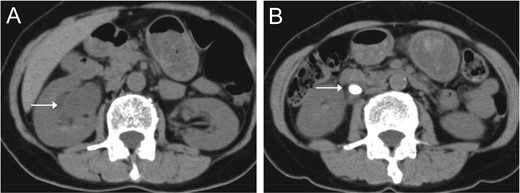

Abdominal CT indicated right hydronephrosis (A) and ureteral stones (B).